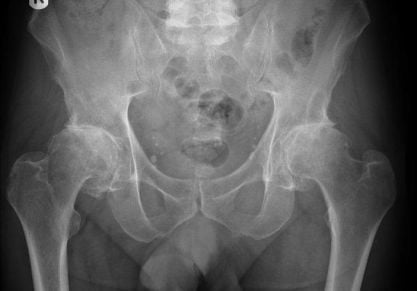

Деформирующий коксартроз тазобедренного сустава: что это такое и как лечить?

Отличия обычного коксартроза от деформирующего. Способы лечения медикаментами и хирургически. Перспективы полного излечения.

• Коксартроз — артроз тазобедренного сустава. Данная разновидность заболевания является лидирующей.